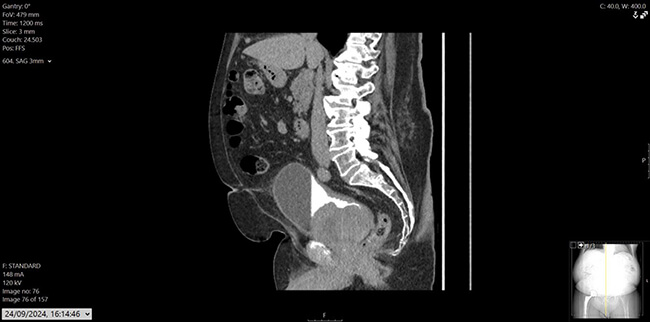

His prostate specific antigen (PSA) had decreased from 43.6ug/L in December 2022 to 0.02ug/L. He also had a history of hypertension, osteoarthritis, and hypercholesterolemia, with mixed lower urinary tract symptoms (LUTS), managed on tamsulosin. Flexible cystoscopy revealed a large mass on the left lateral bladder wall, with CT imaging confirming a bladder mass and thickening at the bladder dome. Mild pericaecal fat stranding and lymphadenopathy were also noted (Figure 1, 2 and 3). Preoperative blood work showed stable parameters.

Figure 3: CT urogram, sagittal.